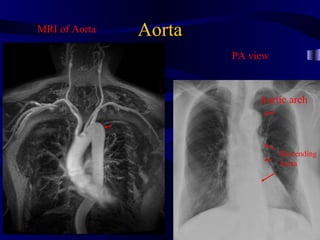

MRI of Aorta Aorta PA view Aortic arch Descending Aorta

Aorta CXR: Lateral View Ascending Descending Aorta Aorta

Case: Aorta canbe enlarged (aneurysm)